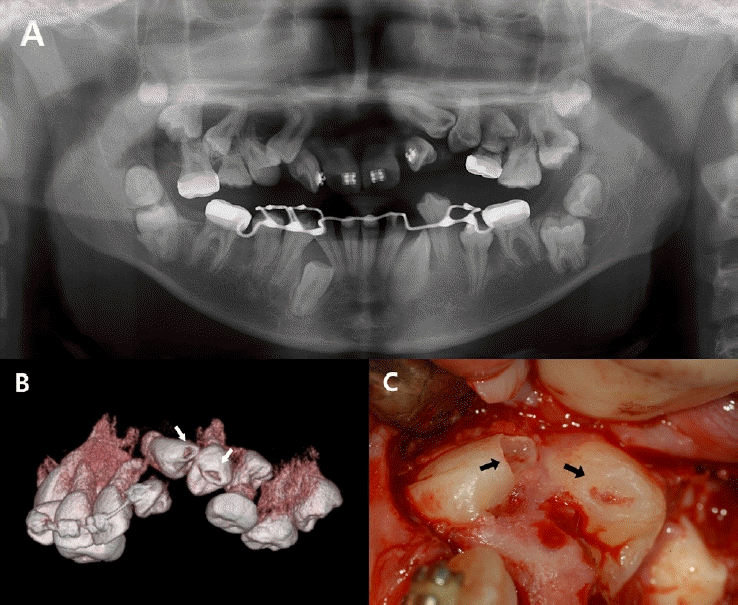

Figure 3.

Preoperative radiographic images and intraoral photographs. A. Panoramic radiograph. B. Cone-beam computed tomography image. C. A coronal defect is identified upon flap reflection.

Figure 4.

Intraoral photographs and intraoral radiograph during treatment. A. Following Biodentine placement. B. Following GI application. C. After approximately 3 months of orthodontic traction, the tooth erupted, and the GI restoration remained intact. D. Periapical radiograph after eruption.

다발성 치아 맹출 장애로 본원에서 치료 중이던 13세 남아에서, 상악 좌측 견치와 제1소구치의 견인을 위한 외과적 노출술 시행 중 두 치아의 치관 교두정 부위에서 부분적 결손이 관찰되었다(Fig. 3C). 환아는 특이한 의학적 병력이 없었으며, 과거 촬영된 방사선 사진에서 해당 치아의 치관부에 방사선 투과상이 관찰되어 PEIR으로 진단하였다(Figs. 3A and B).외과적 노출 시 병소의 입구를 조심스럽게 제거한 결과, 상악 좌측 견치와 제1소구치 모두에서 치수와 개통된 광범위한 흡수성 병소가 확인되었다. 이에 두 치아에 직접 치수 복조술을 시행하였으며, calcium silicate 계열 복조재인 Biodentine (Septodont Corp., Paris, France)을 적용한 뒤, GI (Riva, SDI, Victoria, Australia)를 충전하였다(Figs. 4A and B).이후 11개월 경과 시 견인술을 통해 치아의 맹출이 이루어졌고, 임상 및 방사선학적 검사에서 이상 소견이 관찰되지 않았다(Figs. 4C and D). GI 수복물을 제거하고 접착제(Scotchbond Universal Adhesive, Solventum, St. Paul, MN, USA)를 도포한 후 복합레진(Filtek Z250 Universal Restorative A2, Solventum, St. Paul, MN, USA)을 이용한 영구 수복을 시행하였다. 환아는 이후 장기간 본원에 내원하여 정기적인 경과 관찰을 받았으며, 9년 간의 추적관찰 기간 동안 별다른 증상은 발생하지 않았으며 치관부에 잔존하는 치관부 방사선 투과상은 변화 없이 유지되었다. (Figs. 5A-C). 9년 후 임상검사 상 치관부의 변색 및 방사선 사진 상 삼차 상아질 형성이 관찰되었으며 추가적인 치료는 시행하지 않았다(Figs. 5D and E).- 증례 3